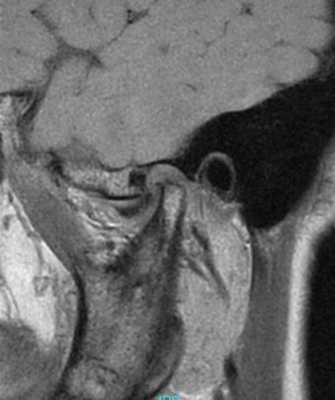

53-летняя женщина с ревматоидным артритом руки, запястья и плеча, обратилась за помощью по причине болевых ощущений в обоих ВНЧС. Она страдала от ревматоидного артрита в течение 1 года и принимала противовоспалительные препараты. КТ-диагностика подтвердила ревматоидное поражение обоих ВНЧС (фото 3а). У пациентки отмечалось ограниченное открывание полости рта (максимально до 23 мм), а болевые ощущения усиливались при движениях нижней челюсти. Для облегчения болевых симптомов было начато изготовление шины и проведен артроцентез обоих ВНЧС. Симптомы улучшились, однако у пациентки медленно начал развиваться передний прикус. Вертикальное перекрытие изменилось от начальных -6 мм до 0 мм (фото 3b).

Фото 3.

а) КТ-срезы, демонстрирующие сплющивание суставных головок, нерегулярность суставной поверхности и сужение суставных пространств.